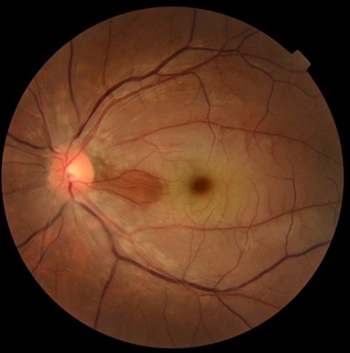

眼底検査では、網膜が白く濁り、中心部(黄斑)にチェリーレッドスポットと呼ばれる赤い点が見られるのが特徴的です。